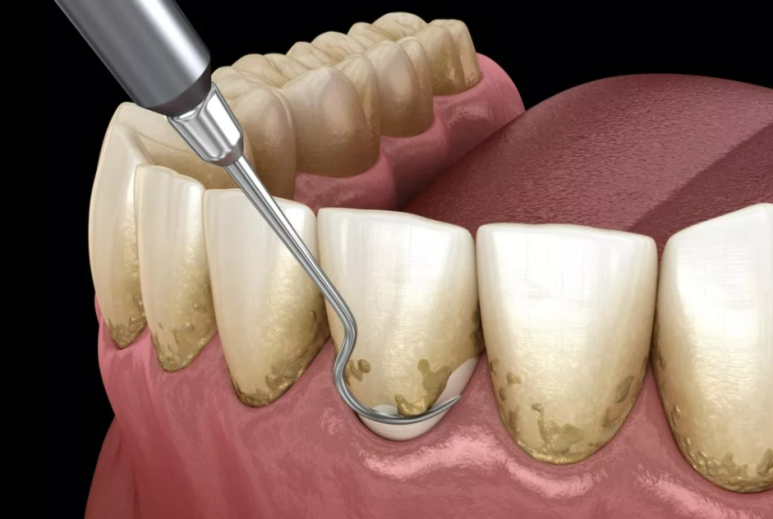

스케일링(치석제거)은 스케일러라는 기구에서 발생하는 미세한 진동을 이용해

치아와 잇몸의 경계와 잇몸 아래 1mm까지 붙어있는 치석과 치태를 제거하는 것이고,

이 스케일러는 치아를 삭제하거나 보철물을 깨뜨릴 수 있는 힘이 존재하지 않기 때문입니다.

위 예시 이미지를 보시면 이해가 잘 되실거라 생각하는데요.

만약 저렇게 잇몸과 치아 경계면에 있는 치석들을 모두 제거했다고 가정한다면,

그 이후엔 잇몸 경계가 좀 더 뚜렷하게 육안으로 확인되면서 더 내려앉은 것처럼 보일 수 있습니다.